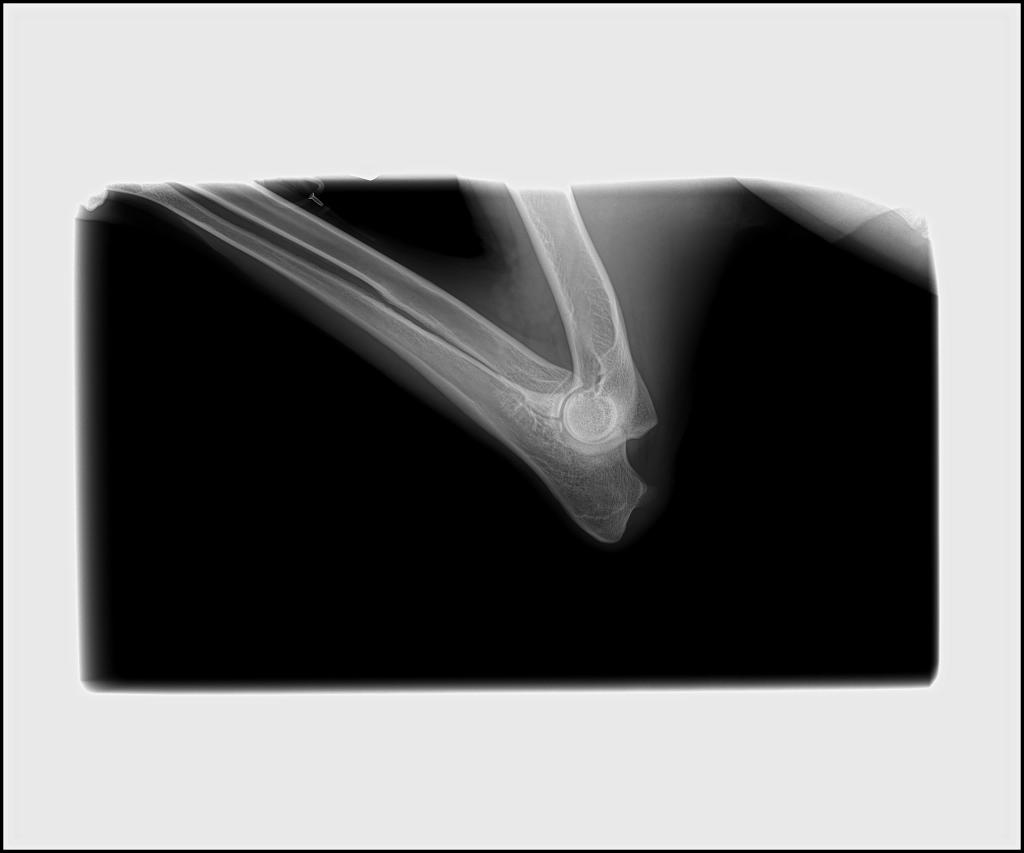

- Hips: OFA Good

- Elbows: OFA Normal

Rocky’s Hip and Elbow X-rays: